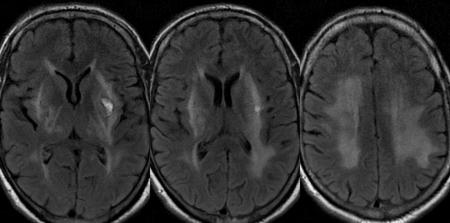

Лейкоэнцефалопатия

При лейкоэнцефалопатии патологическому повреждению подвергается, в основном, белое вещество подкорковых структур головного мозга. При обширных поражениях врачи говорят о перивентрикулярной форме ишемии.

- МРТ;

- КТ;